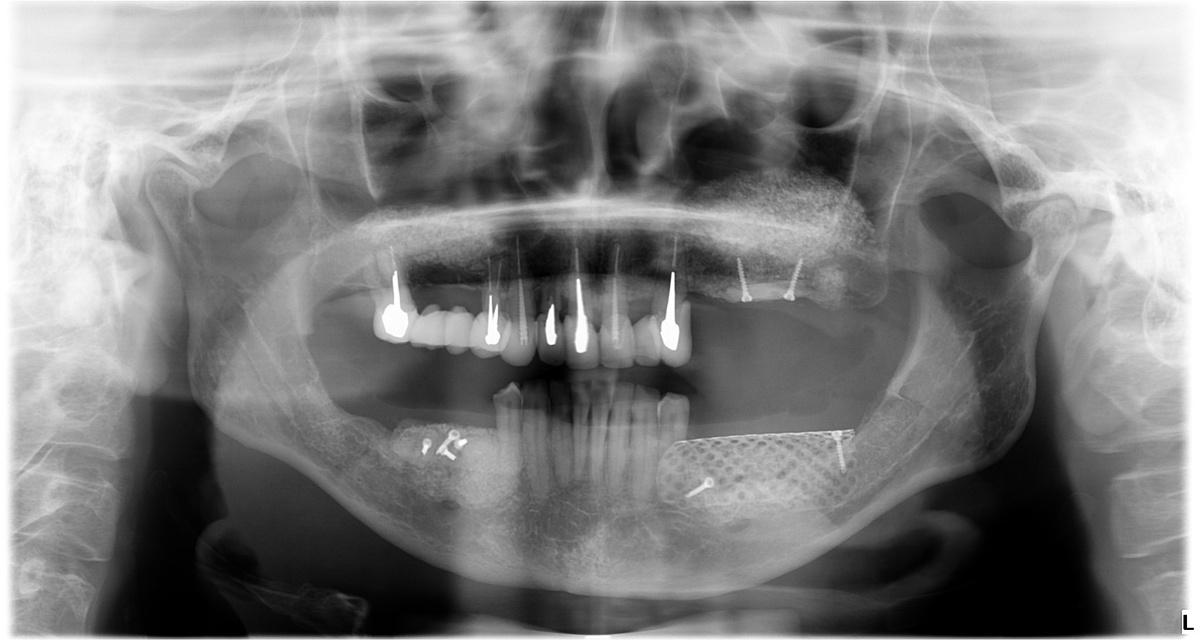

На рентгеновском снимке ситуация в полости рта выглядит следующим образом:

Проблемы:

1 — атрофия костной ткани в области ранее удаленных 5 и 6 зубов на верхней челюсти справа.

2 — атрофия костной ткани до первого витка имплантов в области 4, 5 и 6 зубов на верхней челюсти слева

3 — внушительный «карман» между зубом мудрости и коронкой на импланте, проведение гигиены которого в домашних условиях было невозможно

4 — выраженная атрофия костной ткани, убыль десны, оголение имплантатов, воспаление, гноетечение

5 — экстремальная атрофия костной ткани в области импланта 5-ого зуба, воспаление мягких тканей, гноетечение

6 — симметричный «карман» слева, между зубом мудрости и коронкой на импланте

7 — клиновидные дефекты (абфракции) и закономерная рецессия (опущение) десны

Следующий шаг — реконструкция костной ткани верхней и нижней челюсти. На снимке ОПТГ обозначены области проведенной остеопластики

Результат на снимке ОПТГ:

Остеопластика на нижней челюсти на снимке ОПТГ